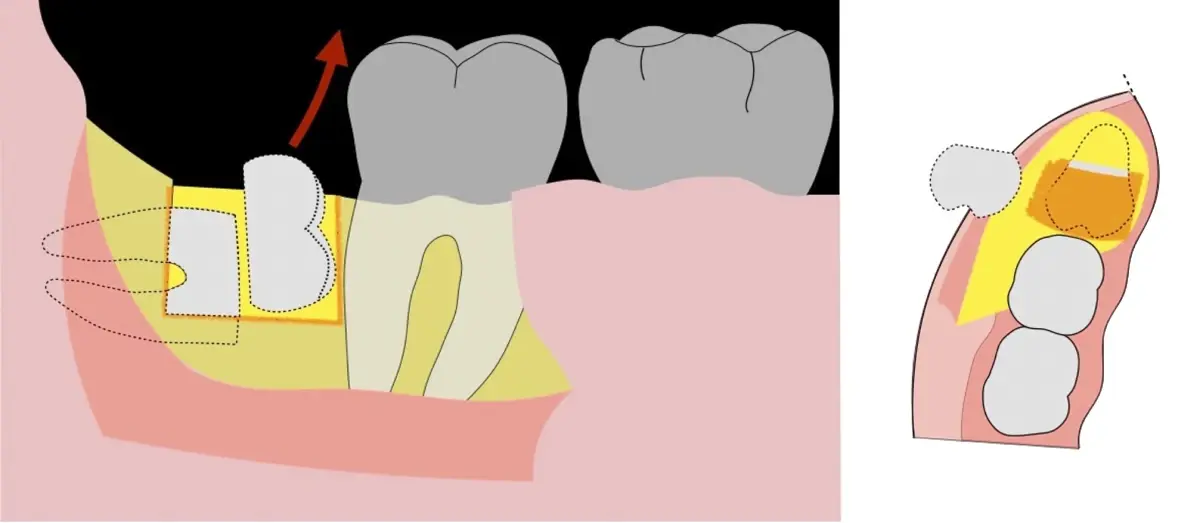

El procedimiento puede variar en su complejidad dependiendo de su ubicación, profundidad, angulación, y la densidad ósea circundante.2 Uno de los pasos más críticos y cruciales en la extracción es la osteotomía previa y concomitante al acceso quirúrgico del diente, para lo cual se utilizan diversos instrumentos como cinceles y martillos, instrumental rotatorio o de corte por ultrasonido.3

En contraste, el instrumento piezoeléctrico utiliza un corte micrométrico que retira un área de superficie mínima de hueso, y reduce el riesgo de termonecrosis marginal en comparación con las fresas rotatorias convencionales.9 Los micromovimientos mejoran la precisión en el corte y el control táctil, y eliminan las macrovibraciones que se producen con los instrumentos rotatorios.10 Su frecuencia de oscilación es la amplitud de 60-200 μm horizontalmente y de 20-60 μm en sentido vertical, lo que es muy inferior en comparación con las micro sierras oscilantes; por lo tanto, proporciona cortes de osteotomía precisos y seguros. Adicionalmente, posee vibraciones ultrasónicas que descomponen el líquido de irrigación en partículas muy pequeñas (fenómeno de cavitación, que produce un efecto hemostático y así reduce la pérdida de sangre), lo que proporciona una visión clara y sin obstáculos del campo quirúrgico11,12.